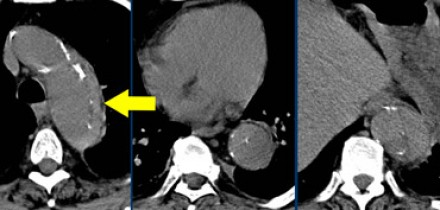

![11]()

- Слева представлен пациент со Stanford A. Диссекция с четкой визуализируемой интимой.

- Справа представлен пациент со Stanford B. Патология локализована в нисходящей аорте. «Точка входа» расположена ниже уровня левой подключичной артерии.

Радиологические находки

- На ниже лежащих снимках представлен пациент с диссекцией типом B. Истинный просвет окружен кальцификацией. Истинный просвет узкий и подвергается компрессионным изменениям, обусловленных систолическим давлением.

- При диссекции аорты интима визуализируется по старым данным только в 70% случаев, но связи с развитием техники данный показатель на сегодняшний день составляет выше 90%.

- На ниже представленных изображениях представлена диссекция типа B.

- Истинный просвет, окружен кальцификатами.

- Истинный просвет уже, чем ложный просвет, а также четко визуализируется симптом клюва.

- В ложном просвете локализован тромб, который контрастируется позже истинного просвета.